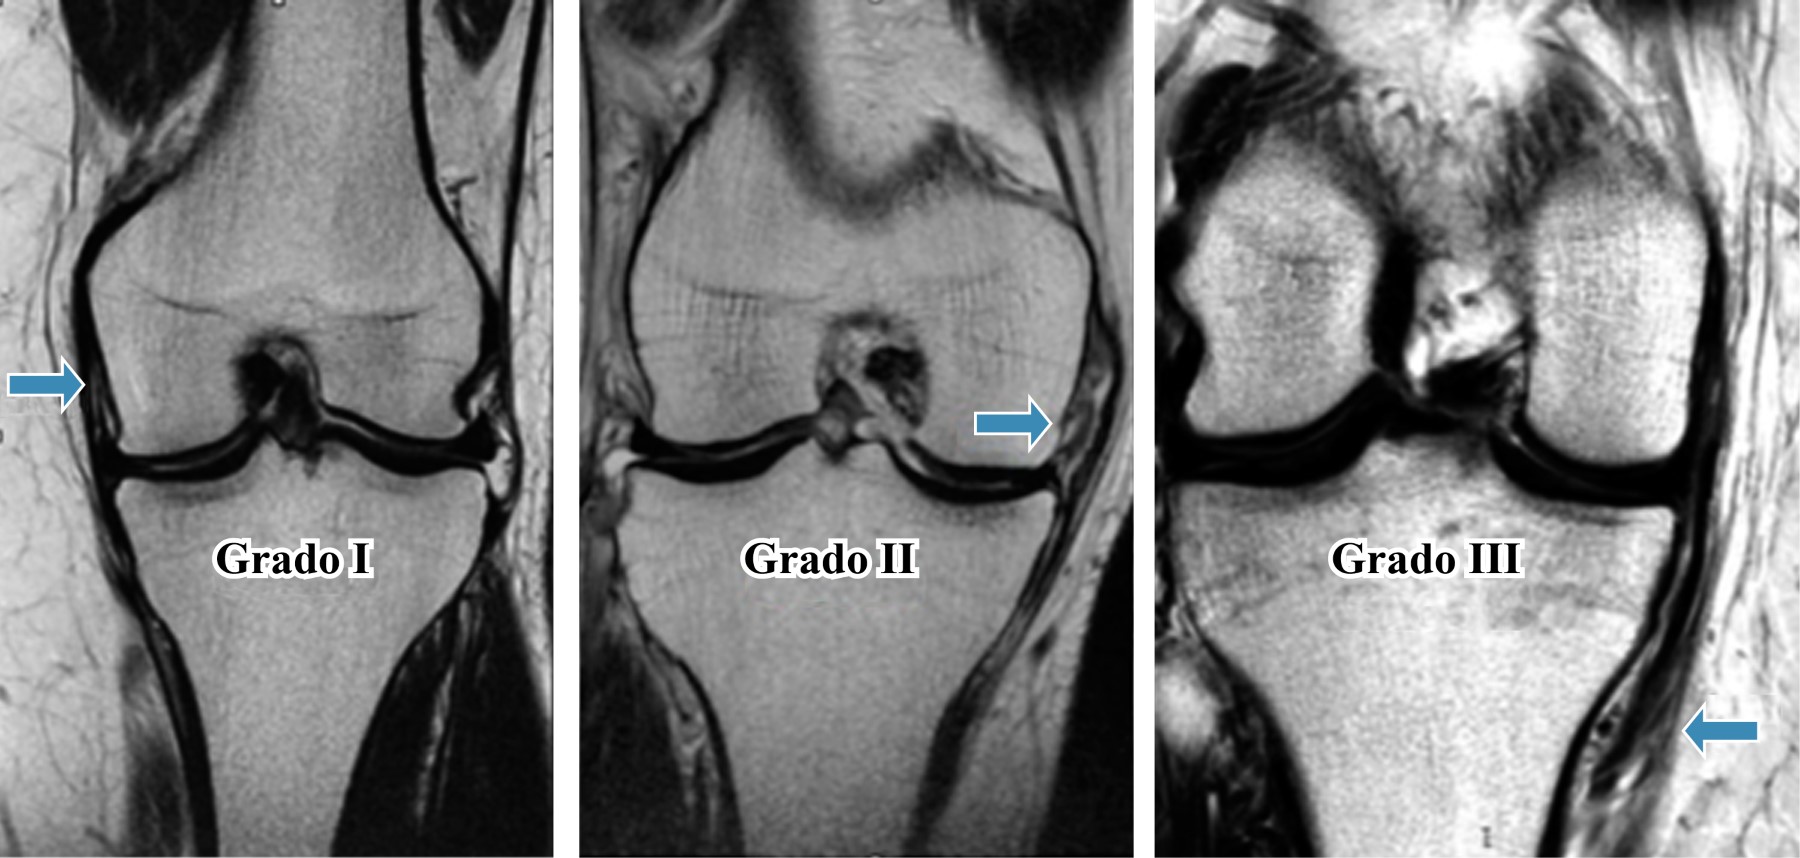

Las lesiones del LCM según la Asociación Médica Americana (AMC por sus siglas en inglés), se dividen en tres grados: el grado I se presenta con hipersensibilidad, pero sin hiperlaxitud. El grado II se manifiesta con sensibilidad localizada y desgarro parcial del LCM y de las fibras oblicuas del ligamento posterior, las cuales continúan opuestas, puede existir laxitud no patológica. En el grado III las fibras tienen una disrupción completa y existe hiperlaxitud al aplicar una fuerza en valgo. Esta clasificación puede ser subjetiva, ya que depende de la capacidad de relajación del paciente y la capacidad del médico para aplicar la fuerza en valgo.1,7 También se pueden clasificar radiológicamente cuando se compara la apertura medial de la articulación contra la extremidad contralateral. El grado I presenta una diferencia de 3 a 5 mm, el grado II va de 6 a 10 mm y el grado III con una diferencia > 10 mm.

EL método de valoración en resonancia magnética que se utilizó fue de acuerdo a la clasificación internacional de lesiones de ligamento medial10 (Tabla 1).

Tuvimos 37 casos (56.9%) de género masculino y 28 casos (43.1%) femeninos, la edad promedio de los pacientes fue de 45.64 años (con un rango de 19-80 años), existía un predominio de lateralidad mayor del lado izquierdo con 38 casos (58.46%). Las lesiones encontradas de grado I fueron en 49 casos (75.38%), de grado II, 10 casos (15.38%) y de grado III, se detectaron dos casos (3.07%), se presentaron cuatro casos (6.15%) de tendinosis del LCM (Figura 1). Las lesiones asociadas halladas fueron lesiones del menisco medial en 30 casos (46.15%), de las lesiones condrales juntas se hallaron 24 casos (36.91%), de fémur fueron 11 casos (16.92%), lesión condal de tibia en nueve casos (13.84%) y lesiones condales de la rótula en cuatro casos (6.15%), lesión del LCA en 20 casos (30.76%), la contusión ósea se observó en 12 casos (18.46%), de la lesión de vasto medial y lesión del retináculo medial se encontraron en nueve casos cada una (13.84%), la lesión del vasto lateral en seis casos (9.23%) y la lesión del LCP en cuatro casos cada una (6.15%), la lesión del menisco lateral y la tenosinovitis de la banda iliotibial se observaron en tres casos (4.61%), fractura de avulsión de la faceta medial y la tenosinovitis de la Pes Anserinus en dos casos (3.07%) y las lesiones del vasto medial, del cuádriceps, lesión del tendón poplíteo, tendón patelar, ruptura del semimembranoso, de la cápsula articular así como las fracturas de la cabeza del peroné y del polo inferior de la patela sólo se encontraron en un caso (1.53%) cada uno. Sólo se detectaron dos casos (3.07%) que presentaban exclusivamente una lesión aislada del ligamento colateral medial y fueron uno de grado I y uno de grado II respectivamente.

Para la valoración imagenológica del ligamento colateral medial, la mejor adquisición es la proyección coronal, la cual nos permite valorar la morfología, intensidad de señal, tensión, dirección y la inserción tibial y femoral. El ligamento colateral medial o ligamento colateral interno se observa hipointenso en todas las secuencias.